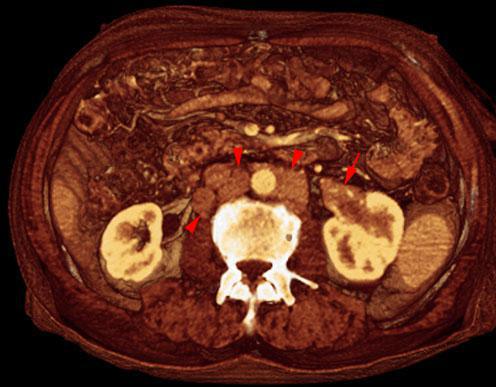

La diferenciación radiológica precisa un estudio de su localización, tamaño, densidades intratumorales, extensión, comportamiento con el contraste, afectación vascular y existencia de adenopatías locorregionales asi como afectación suprarrenal o metastásica.

Es indispensable una aproximación prequirúrgica que determine la vascularización aterial y venosa de los riñones